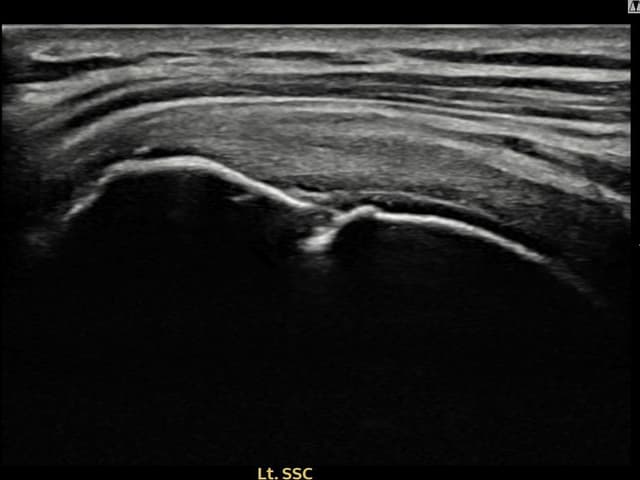

[経過期間: 23.07.18~23.09.14]

[縫縮術] 超音波検査にて左 棘上筋腱 광범위 部分断裂(15mm × 6mm (腱厚の約70%欠損))を確認。縫縮術施行後、腱の連続性が回復し、日常生活に復帰されました。